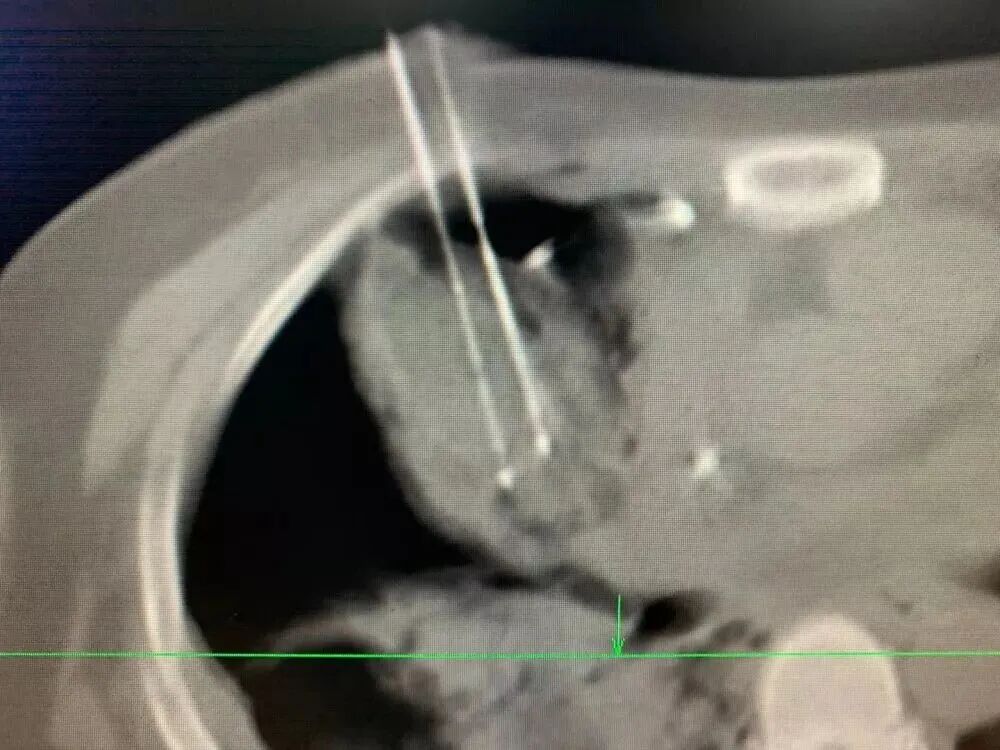

之前有一位腸癌患者,經(jīng)歷手術(shù)和放化療后,發(fā)生了肺轉(zhuǎn)移。腫瘤雖然不大,卻長在了心臟旁邊。如果直接開刀,風(fēng)險極高;直接做冷凍消融,又可能誤傷心臟。最終我們決定采用“釣魚執(zhí)法”冷凍消融術(shù)。

手術(shù)中,我用一根冷凍針“釣”住腫瘤,像收起魚線那樣,慢慢把它從心臟附近牽引到更安全的位置,再實施冷凍消融。整個過程必須極度謹(jǐn)慎,因為心臟周圍血管豐富,稍有不慎就可能引發(fā)大出血。

類似的情況還包括長在肺門附近的結(jié)節(jié),位置也非常棘手。借助冷凍固定和“釣魚”技巧,使結(jié)節(jié)遠離肺門大血管,再插入活檢針和冷凍針,就能安全、徹底地消滅它。